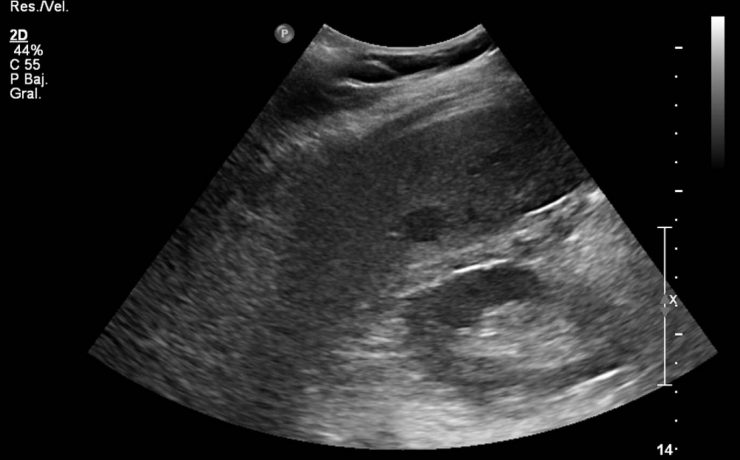

Estudio correlacional entre el índice de masa corporal, perímetro abdominal y volumen de la glándula prostática en pacientes con sintomatología obstructiva urinaria por crecimiento prostático

Antecedentes: La hiperplasia prostática benigna es una enfermedad que se caracteriza desde el punto de vista clínico por una serie de signos y síntomas del tracto urinario bajo (LUTS, por sus siglas en inglés) debido al crecimiento de la próstata. La obesidad es la acumulación